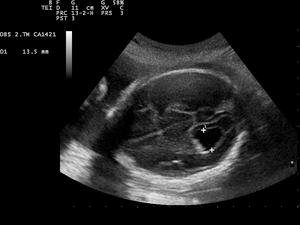

Prenatal ultrasound showing a well defined hypoechoic lesion corresponding to a choroid plexus cyst | |

Choroid plexus cysts (CPCs) are cysts that occur within choroid plexus of the brain. The brain contains pockets or spaces called ventricles with a spongy layer of cells and blood vessels called the choroid plexus. This is in the middle of the fetal brain. The choroid plexus has the important function of producing cerebrospinal fluid. The fluid produced by the cells of the choroid plexus fills the ventricles and then flows around the brain and the spinal cord to provide a cushion of fluid around these structures.

CPCs can form within this structure and come from fluid trapped within this spongy layer of cells, much like a soap bubble or a blister. CPCs are often called "soft signs" or fetal ultrasound "markers" because some studies have found a weak association between CPCs and fetal chromosome abnormalities.